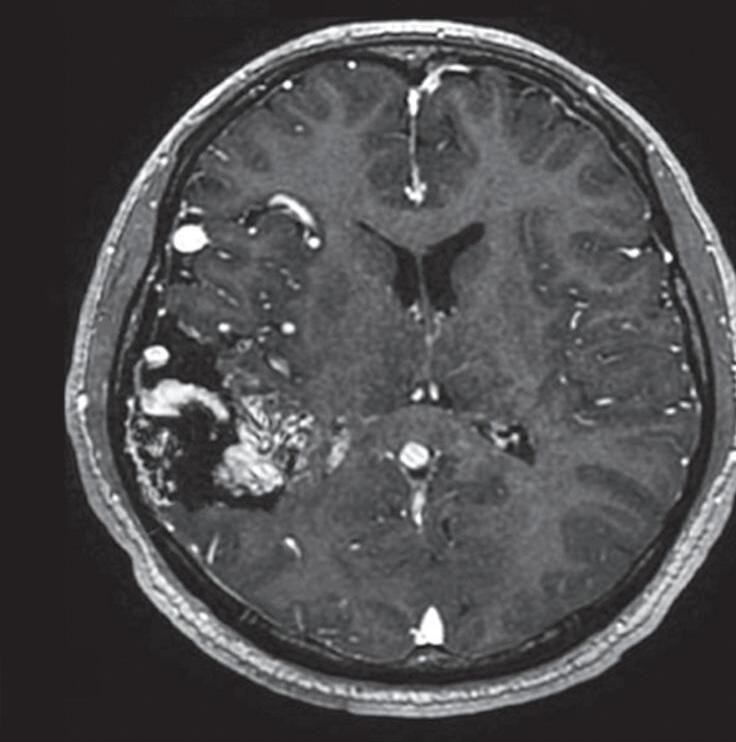

A soma dos pontos de cada um desses três critérios resulta em uma pontuação total, que ajuda a determinar a gravidade da MAV e, assim, a abordagem terapêutica a ser instituída. Cada grupo da classificação de Spetzler-Martin demonstra graus variáveis de risco e complexidade, com implicações diretas na escolha do tratamento. A seguir, exemplos de cada um dos cinco graus desta classificação: grau 1 (Fig. 1-13), grau 2 (Fig. 1-14), grau 3 (Fig. 1-15), grau 4 (Fig. 1-16), grau 5 (Fig. 1-17). A classificação de EM pode gerar uma combinação de resultados e ser utilizada para nortear o tratamento. Apesar de ter sido, na época, um grande avanço na avaliação e no tratamento das MAVs cerebrais, a classificação de Spetzler-Martin necessitou ser modificada, em virtude dos avanços no diagnóstico e no tratamento dessas lesões. Em 2010, Lawton propôs essa mudança objetivando facilitar mais ainda a tomada de decisão terapêutica das MAVs.28 Assim, o novo sistema possibilita uma melhor análise do padrão de drenagem venosa, por exemplo. Então, com base nesse critério, malformações de pequeno tamanho localizadas em áreas não eloquentes, com drenagem venosa profunda, são mais complexas de tratar do que as MAVs grandes, localizadas em áreas eloquentes, porém sem comprometimento da drenagem venosa ou que apresentem um sistema de drenagem

Fig. 1-14. RNM encéfalo, T2 axial (a) e coronal (b), demonstrando MAV grau 2 no lobo parietal esquerdo.

Arteriografia cerebral (c) AP e (d) em perfil, demonstrando a irrigação pelos ramos da artéria cerebral média (ACM) e anterior (ACA), com drenagem pela veia de Labbé, no seio transverso sigmoide.